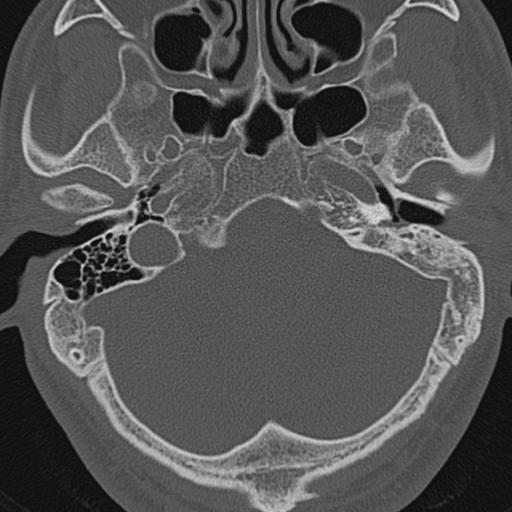

以下是引用zxl51642在2009-8-25 13:37:00的发言:[br]1、左侧慢性硬化型中耳乳突炎(中耳鼓室腔及听小骨受累),并胆脂瘤形成;2、左侧外耳道软组织密度影填塞,考虑炎性肉芽肿,建议结合临床;3、右侧颈静脉窝较左侧明显扩大,不排除颈静脉球瘤,建议mr进一步检查。

以下是引用随光逐影在2009-8-25 19:05:00的发言:[br]1)左侧慢性中耳乳突炎(肉芽肿或胆脂瘤形成),左侧外耳道炎性肉芽肿。2)右侧颈静脉球高位。